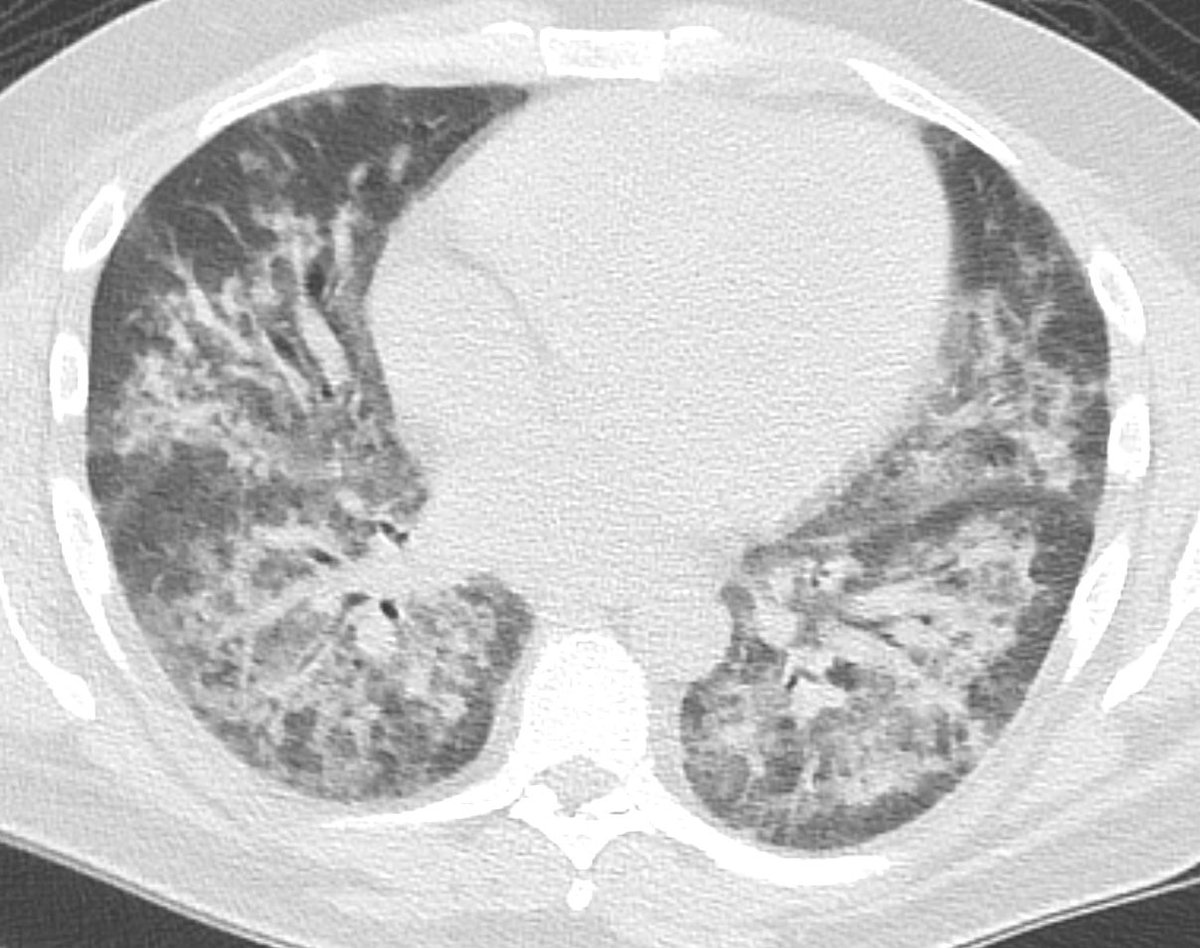

Here are the lung windows, showing pretty typical right lower lobe pneumonia. Does this change your thinking about the first image? Note that there is no interstitial edema in the RLL or pleural effusion.

If we look at lung windows, decreased perfusion through the right lung can be appreciated as diffusely decreased density of the right lung. Interestingly this involves much more lung than just the area of pneumonia - here much of the right lung is affected.

Another important thing to think about here - if this was a big thrombus in the right inferior pulmonary vein, there would be significant interstitial edema/septal thickening in the right lower lobe, and probably an effusion. These are not present.